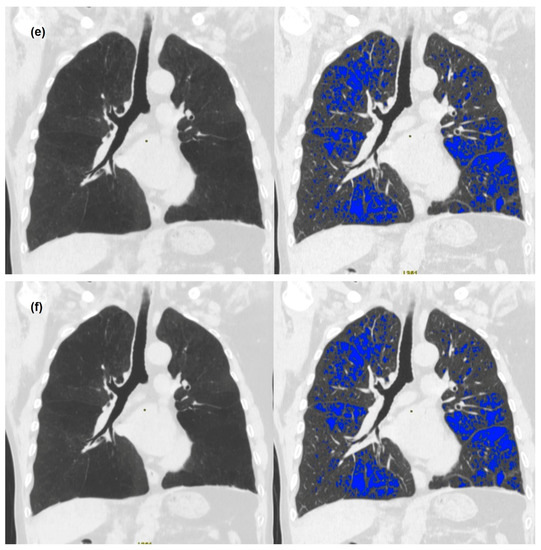

3. Results

3.2. Quantitative Measurements of Standard-Dose and Ultra-Low-Dose CT

4. Discussion